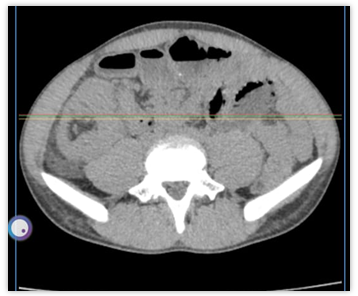

We report here a case of a 21 y old male patient who presented to the casualty with complaints of severe abdominal pain, nausea, vomiting, and loose motion for the past week. Upon a general physical examination, the patient had a slightly increased fever, tachycardia, and short, frequent breaths. On local examination, the abdomen was mildly distended and tender, with the presence of voluntary guarding on palpation. No mass was palpated per abdomen. Tenderness was more prominent on the right side. On digital rectal examination, no palpable mass was felt, and the glove was stained with reddish-yellow fecal matter. The patient was immediately admitted and kept NPO until further order; a 16-fr RT was inserted with continuous aspiration; and a 16-fr Foley’s catheter was connected to monitor the urine output. Intravenous fluid was started, and a prophylactic 3rd-generation cephalosporin was started along with injectable metronidazole, proton pump inhibitors, and analgesics. A complete blood hemogram and an ultrasonography of the abdomen were advised for the initial assessment. Ultrasonography of the abdomen and pelvis showed concentric rings of bowel loops in the right iliac fossa, suggestive of ilio-colic intussuption with no proximal dilation of bowel loops. There is symmetrical mural thickening of the bowel wall of the ascending colon with few sub-centimetric lymphnodes around the right iliac fossa. In view of the above, a CT scan of the whole abdomen (fig. 1A and 1B) was advised, which suggested subacute intestinal obstruction with large Ileo-colic intussusception with 3.5 x 3.0 cm of soft tissue as the lead point.

Fig. 1A and 1B: Photograph showing SAIO with large Ileo-colic intussusception with a 3.5 x 3.0 cm soft tissue as the lead point]